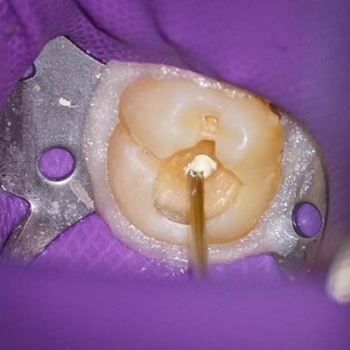

Izolarea a fost realizată folosind o digă de cauciuc, o clemă din oțel inoxidabil și digă lichidă fotopolimerizabilă plasată în jurul clemei pentru a preveni contaminarea bacteriană a zonei de tratat. Caria a fost îndepărtată circumferențial de la marginea coronară spre marginea cervicală pentru a limita intrarea bacteriilor în spațiul țesutului pulpar (9). O explorare a podelei cavității a arătat o expunere a pulpei (Figurile 3 și 4). Este întotdeauna recomandabil să explorați podeaua cavității cu un endoexplorator, deoarece o deschidere mică a camerei pulpare poate fi trecută cu vederea.

În cazurile în care există hemoragie în regiunea pulpară expusă, este necesar să se aplice o presiune susținută timp de 40-60 de secunde cu o buletă de vată umezită cu soluție salină sterilă (10), urmată de dezinfectarea cavității cu hipoclorit de sodiu 0,5%. După aceasta, materialul bioactiv Biodentine a fost plasat pentru a acoperi direct pulpa (Fig. 5 și 6), materialul a fost plasat vrac ca înlocuitor dentinar. Deoarece materialul face priză în 12 minute, a fost posibilă și restaurarea în aceeași ședință (11). Restaurarea definitivă s-a făcut ulterior, folosind rășină compozită cu tehnica stratului oblic (Fig. 7) cu scopul de a minimiza contracția materialului (12).

Fig. 3. & Fig. 4. Expunerea pulpară la nivelul podelei cavității, cu hemoragie minimă ușor de controlat.

Fig. 5. & Fig. 6. Plasarea vrac a Biodentinei cu ajutorul unui compactor endodontic.